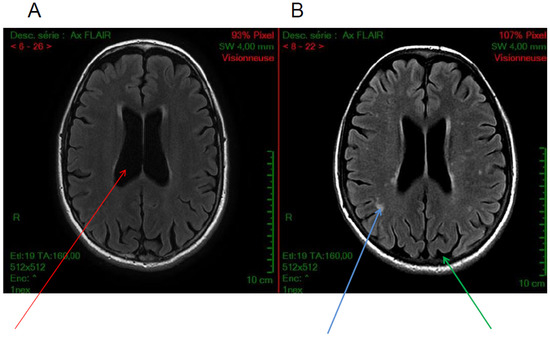

Figure 2.

Axial FLAIR sequences. Examples of brain MRI anatomical images of cystinosis patients showing (A) an isolated ventricular dilatation (red arrow), (B) in another patient, cortical atrophy (green arrow) and diffuse white matter anomalies (blue arrow) associated with ventricular dilatation, (C–F) diffuse subcortical white matter hyperintensities, and (G,H) Wirshow or perivascular space enlargement (blue arrow)(images from N. Boddaert, Necker hospital).

Cortical atrophy is the most frequent radiological finding in cystinosis patients. By computed tomography (CT) scan or magnetic resonance imaging (MRI), cortical atrophy is observed in almost all patients with CNS symptoms [7]. Cerebral atrophy is also reported in patients without important CNS clinical abnormality and in patients with minor alterations in cognitive performance, in particular with impairment of visual memory [15,36,39]. In a recent study, among patients with infantile cystinosis, 72% showed evidence of cortical atrophy, 67% central atrophy (ventriculomegaly), and 50.0% demonstrated both (Figure 2) [17]. In that study, only two patients with infantile cystinosis had a normal brain MRI, both being the youngest patients included. Interestingly, no atrophy was observed in patients with late-onset cystinosis, even if the patients analyzed were older than the other cystinosis patients. Importantly, such atrophy was specifically observed in cystinosis patients, and not in controls with nephropathy. In another study, also including younger patients, cystinosis patients presented significantly more atrophy than age- and sex-matched healthy controls in the frontal, parietal, temporal, and occipital regions, the corpus callosum, and the cerebellum [35]. It is worth noticing that atrophy was localized in parieto-occipital regions, which is consistent with the visuo-spatial-specific impairment described in these patients.

5.3. White Matter Hyperintensities

White matter hyperintensities can be observed in 50% of cystinosis patients, including in patients with adolescent onset cystinosis (Figure 2) [17,35]. However, we have recently shown that these hyperintensities can also be observed in other patients with chronic renal failure [17]. White matter anomalies have been reported in some previous studies [7,40]. Interestingly, white matter abnormalities have been described in adults with chronic kidney disease compared to controls, suggesting that chronic kidney disease may result in a brain phenotype consistent with accelerated aging [35,41,42]. These results demonstrate the importance of adding a control group with renal failure when investigating brain abnormalities in cystinosis patients.